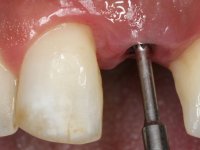

O ajuste final da cor/shade da restauração directamente em boca têm grande importância no sucesso do tratamento. Qualquer alteração necessária pode ser realizada nesta fase. As tonalidades de dentina e incisais foram aplicadas em conjunto de acordo com o esquema de estratificação visando a sua caracterização individualizada, mas ainda não foi aplicada a camada de superfície que dá translucidez á restauração. Este facto, permite que possíveis deficiências na cor/shade possam ser corrigidas removendo porções de cerâmica que apresentem tonalidades indesejadas. O brilho/brightness da primeira camada não deve ser muito baixo, porque pode fazer com que a restauração apresente um aspecto acinzentado. Esta situação pode ser contornada utilizando uma pastilha um pouco mais clara do que a cor/shade que se pretende para o resultado final.

Neste caso a paciente foi vista no laboratório, o que tornou possível estabelecer o correcto nível de saturação da cor e brilho. Quando a construção da cerâmica estava optimamente ajustada em termos de cor/shade, os componentes da translucidez puderam ser finalmente acrescentados. Nesta fase foi também completada a anatomia e a textura superficial de acordo com a informação dada pelos detalhes reproduzidos no modelo. A caracterização com tonalidades e essências no ciclo final de cozedura é fundamental, permitindo um ajuste fino da caracterização.